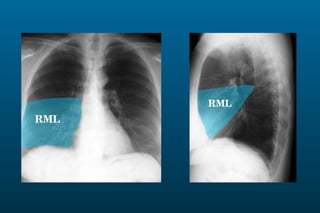

1) The posterior-anterior (PA) view is the standard and most reliable technique for a chest x-ray. It allows detection of air under the diaphragm. 2) A lateral view helps localize infiltrates and evaluate the cardiomediastinal silhouette, effusions, and left atrial dilation. 3) An anterior-posterior (AP) view is used when a patient is too ill to be transported, but image quality is poorer and structures may appear enlarged compared to a PA view.